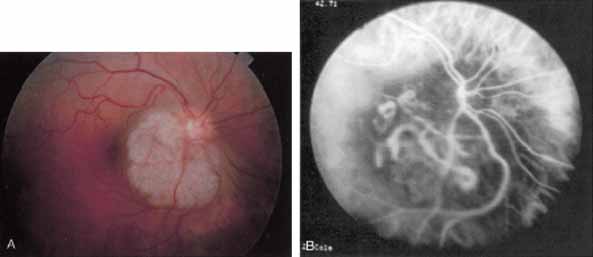

In acute multifocal posterior placoid pigment epitheliopathy, discrete hypofluorescent geographic areas are present both in the posterior pole and extending into the mid-periphery on ICG angiography65,66 (Fig. 16). These hypofluorescent areas are more extensive than noted on either clinical or fluorescein angiographic examination. They are noted in the early phases of the ICG study and persist late, suggesting that ischemic changes in the choroidal circulation occur in this disease. The hypofluorescence remains even once lesions have healed.

Fig. 16 A. Clinical photograph of a patient with acute multifocal placoid pigment epitheliopathy (AMPPE). There is extensive involvement of the central macula by the inflammatory lesions. B. Late-phase indocyanine green angiogram demonstrating extensive confluent but irregular areas of marked hypofluorescence. The hypofluorescence in AMPPE is believed to represent a perfusion abnormality within the choroidal circulation.